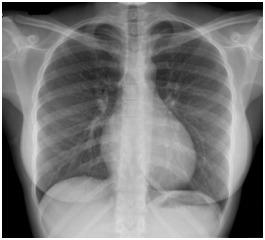

Radiographie thoracique normale

2. Radiographie thoracique normale